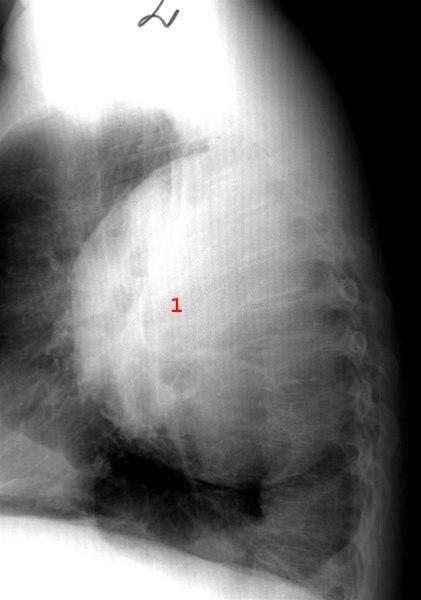

Lungeabscess - side

Svær lungeabscess, pussfylt hule i lungen (1)